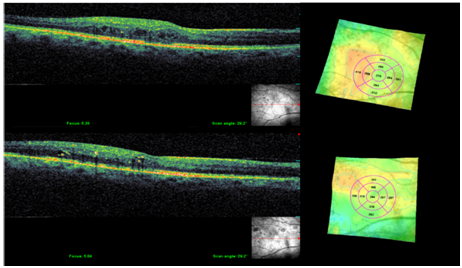

Figure 2 Shows NON central CSME in topography and tomography before (above) and after (bottom) treatment with subthreshold 532 nm laser showing that laser has reduced macular thickening and maintained BCVA 20/20 without causing central edema progression or retinal thermal damage, this patient had an average HbA1C 8% there for required repeat treatment at week 16.